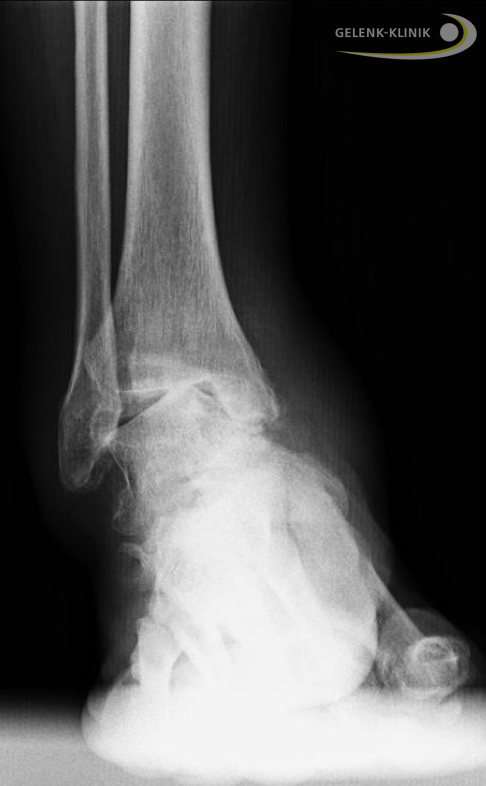

Varusstellung des Rückfußes: Das Fersenbein kippt nach innen

Die Verkippung des Fersenbeins nach innen führt zu einer Überlastung. Häufig schädigt dies auch die Außenbänder: Weil sich die Beinachse nach außen verlagert, müssen die Außenbänder viel mehr Last tragen.

Zudem kann diese Steilstellung der Ferse zu Reizungen der Weichteile führen. Hier können Schleimbeutelentzündungen im Bereich des Achillessehnenansatzes entstehen. Überbeine (Exostosen) an der Ferse, auch Haglundexostosen genannt, können daraus resultieren. Durch die Fehlstellung des Rückfußes beim Hohlfuß entstehen an der Ferse besonders häufig chronische Schmerzen.

Bildgebende Diagnostik: Röntgen, DVT, MRT

Auf Röntgenbilder finden wir eindeutige Hinweise auf degenerative Veränderungen von Sprunggelenk und Fußgelenken. Unter Belastung – also im Stehen – können wir zudem eine Fehlstellung des Fersenbeines in mehreren Ebenen auf den Bildern zeigen. Des Weiteren untersuchen wir die Vorfußstellung im Verhältnis zum Rückfuß.